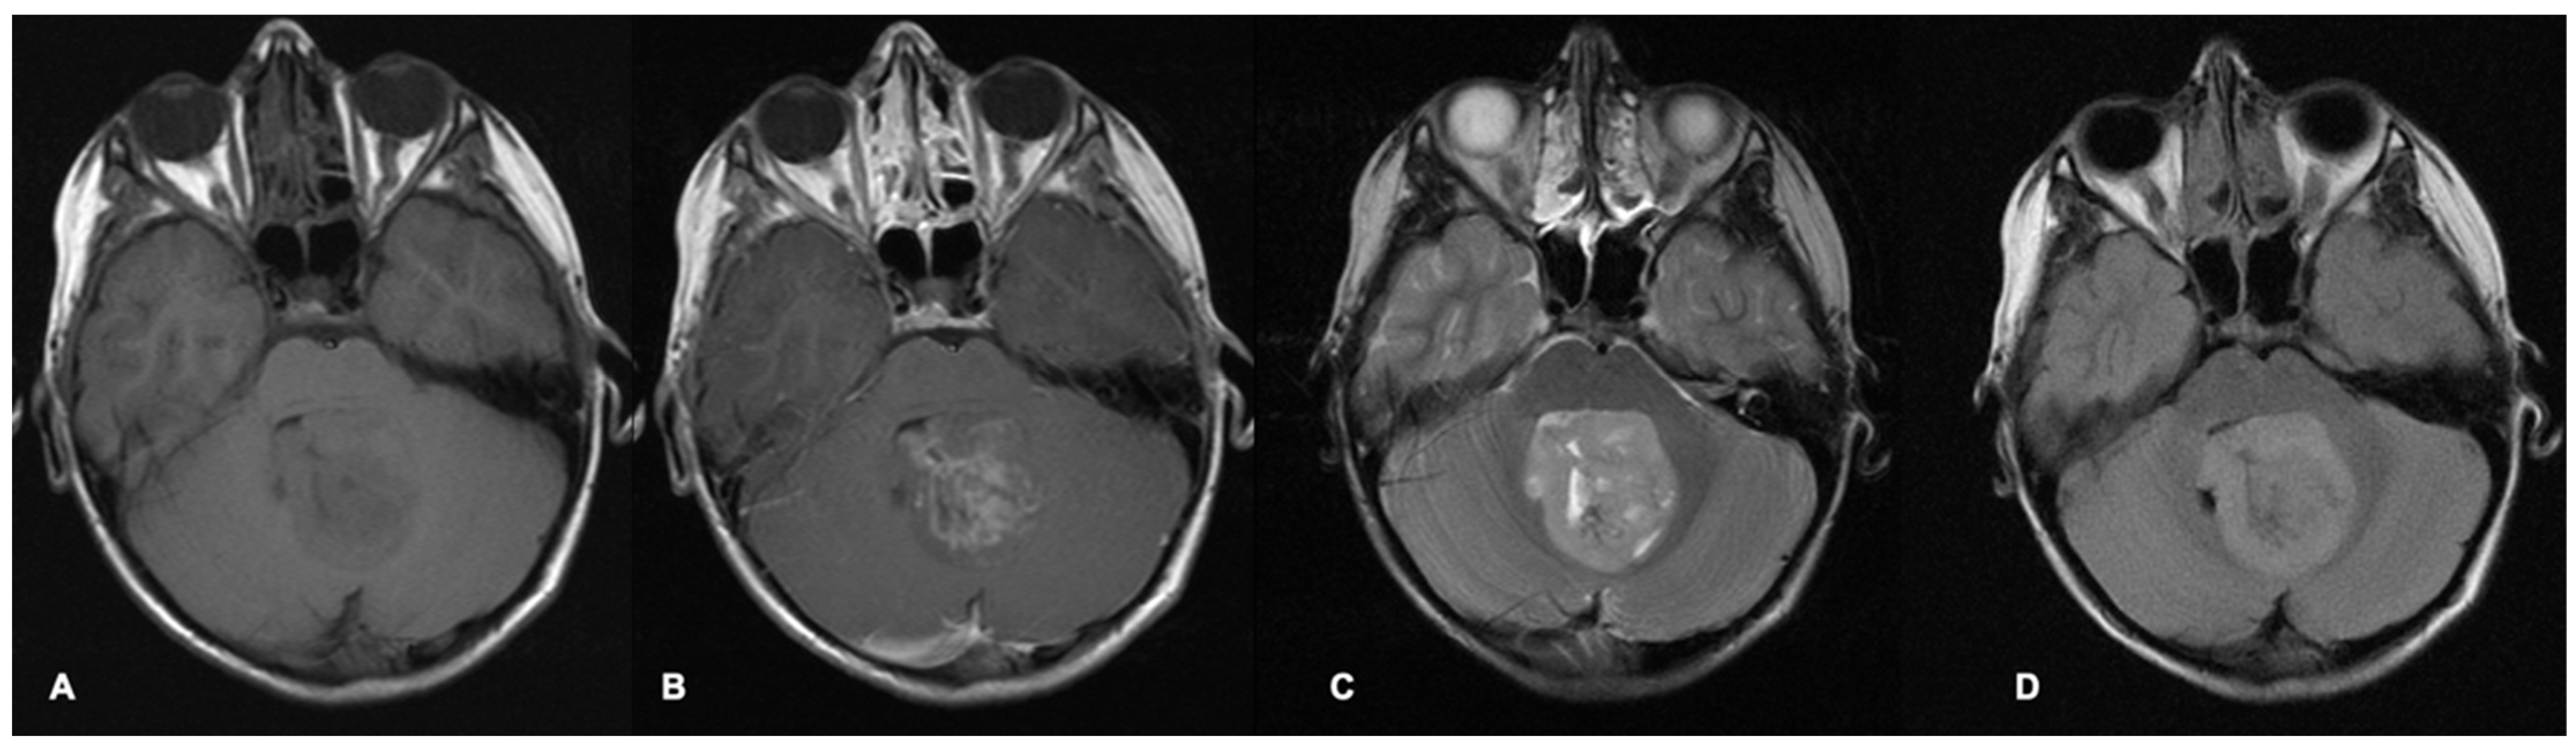

MRI scans are the most common imaging modality used for investigation, treatment-planning and surveillance of brain tumours. Different MRI sequence acquisitions can display many characteristics of tumours and the surrounding brain as well as help distinguish tumours from other differential diagnoses (Figure 1 and Figure 2). Radiological features including tumour size, location, enhancement patterns and heterogeneity as well as the presence of cysts, necrosis, haemorrhage, and calcification aid radiologists’ prediction of tumour type (Table 1) [22].

Figure 1.

Axial MRI brain scan of a fourth-ventricle medulloblastoma in a 9-year-old boy. The pre-contrast T1 sequence (A) shows a heterogenous hypointense tumour filling and expanding the fourth ventricle, which demonstrates patchy contrast enhancement on the post-contrast T1 (B). The tumour appears mostly hyperintense with some heterogeneity on the T2 (C) and FLAIR sequence (D). FLAIR = fluid-attenuated inversion recovery.